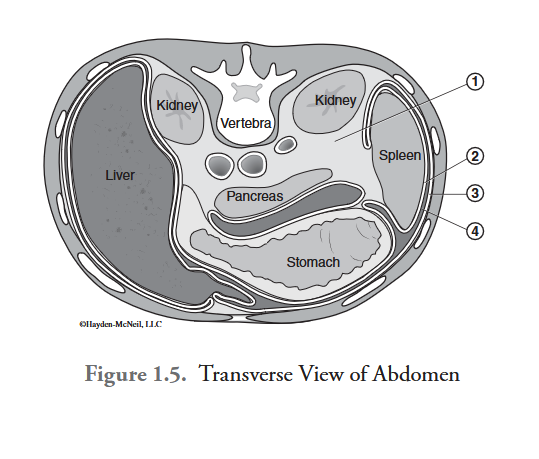

What is labeled #1?

retroperitoneal space

What is labeled #2?

visceral peritoneum

What is labeled #3?

parietal peritoneum

What is labeled #4?

peritoneal cavity